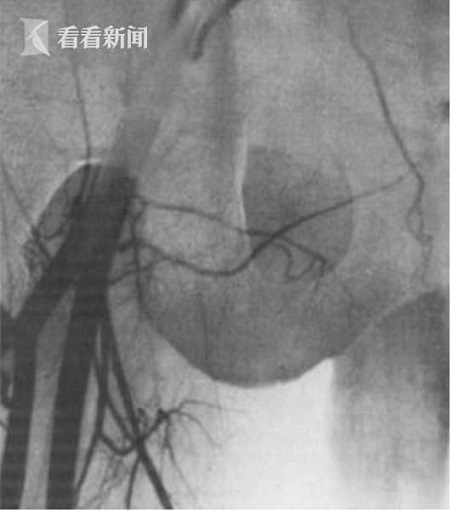

男子沒(méi)“蛋蛋”無(wú)法生育 兄長(zhǎng)自愿捐助移植成功

近日,在塞爾維亞的一家醫(yī)院進(jìn)行了一場(chǎng)不同尋常的手術(shù)。一名36歲男子因先天沒(méi)有睪丸,導(dǎo)致其無(wú)法生育,為了一圓其當(dāng)爸爸的夢(mèng)想,雙胞胎哥哥自愿捐助一顆睪丸。經(jīng)過(guò)國(guó)際醫(yī)療團(tuán)隊(duì)長(zhǎng)達(dá)6小時(shí)的高風(fēng)險(xiǎn)手術(shù)后,睪丸移植宣告成功,讓該名男子終于有了生育能力。

綜合外媒報(bào)道,該名36歲的塞爾維亞男子和哥哥是同卵雙胞胎,遺憾的是在母體胎盤(pán)中時(shí),細(xì)胞沒(méi)有完整分裂,導(dǎo)致在出生時(shí)就沒(méi)有睪丸。雖然當(dāng)哥哥的自愿捐助一顆睪丸,但是由于手術(shù)難度堪稱(chēng)世界級(jí),遲遲沒(méi)有醫(yī)生敢動(dòng)刀。直到近日,一位美國(guó)名醫(yī)率隊(duì)飛到塞爾維亞,為他進(jìn)行長(zhǎng)達(dá)6小時(shí)的手術(shù),移植才宣告成功。

這位名叫喬爾杰維奇的醫(yī)生任職于美國(guó)紐約西奈山醫(yī)院性別重置專(zhuān)科,上周率領(lǐng)國(guó)際醫(yī)療團(tuán)隊(duì)飛抵塞爾維亞首都貝爾格萊德,親自操刀實(shí)施手術(shù)。

手術(shù)期間,醫(yī)療團(tuán)隊(duì)必須同時(shí)將雙胞胎兄弟的陰囊切開(kāi),進(jìn)行睪丸移植,并在極為有限的時(shí)間內(nèi),將陰囊內(nèi)的兩根動(dòng)脈、兩根寬不到兩毫米的靜脈成功縫合。

另?yè)?jù)專(zhuān)業(yè)人士介紹稱(chēng),一旦把睪丸從捐贈(zèng)者體內(nèi)取出后,必須在之后的2到4個(gè)小時(shí)內(nèi),重新“接上線”。睪丸在無(wú)血液注入的情況下,最多只能存活6個(gè)小時(shí)。

手術(shù)后,這對(duì)匿名的塞爾維亞兄弟恢復(fù)情況良好,各項(xiàng)生理指標(biāo)也重回正常水平。由于捐贈(zèng)者和受捐贈(zèng)者為雙胞胎,未引發(fā)排異反應(yīng)。